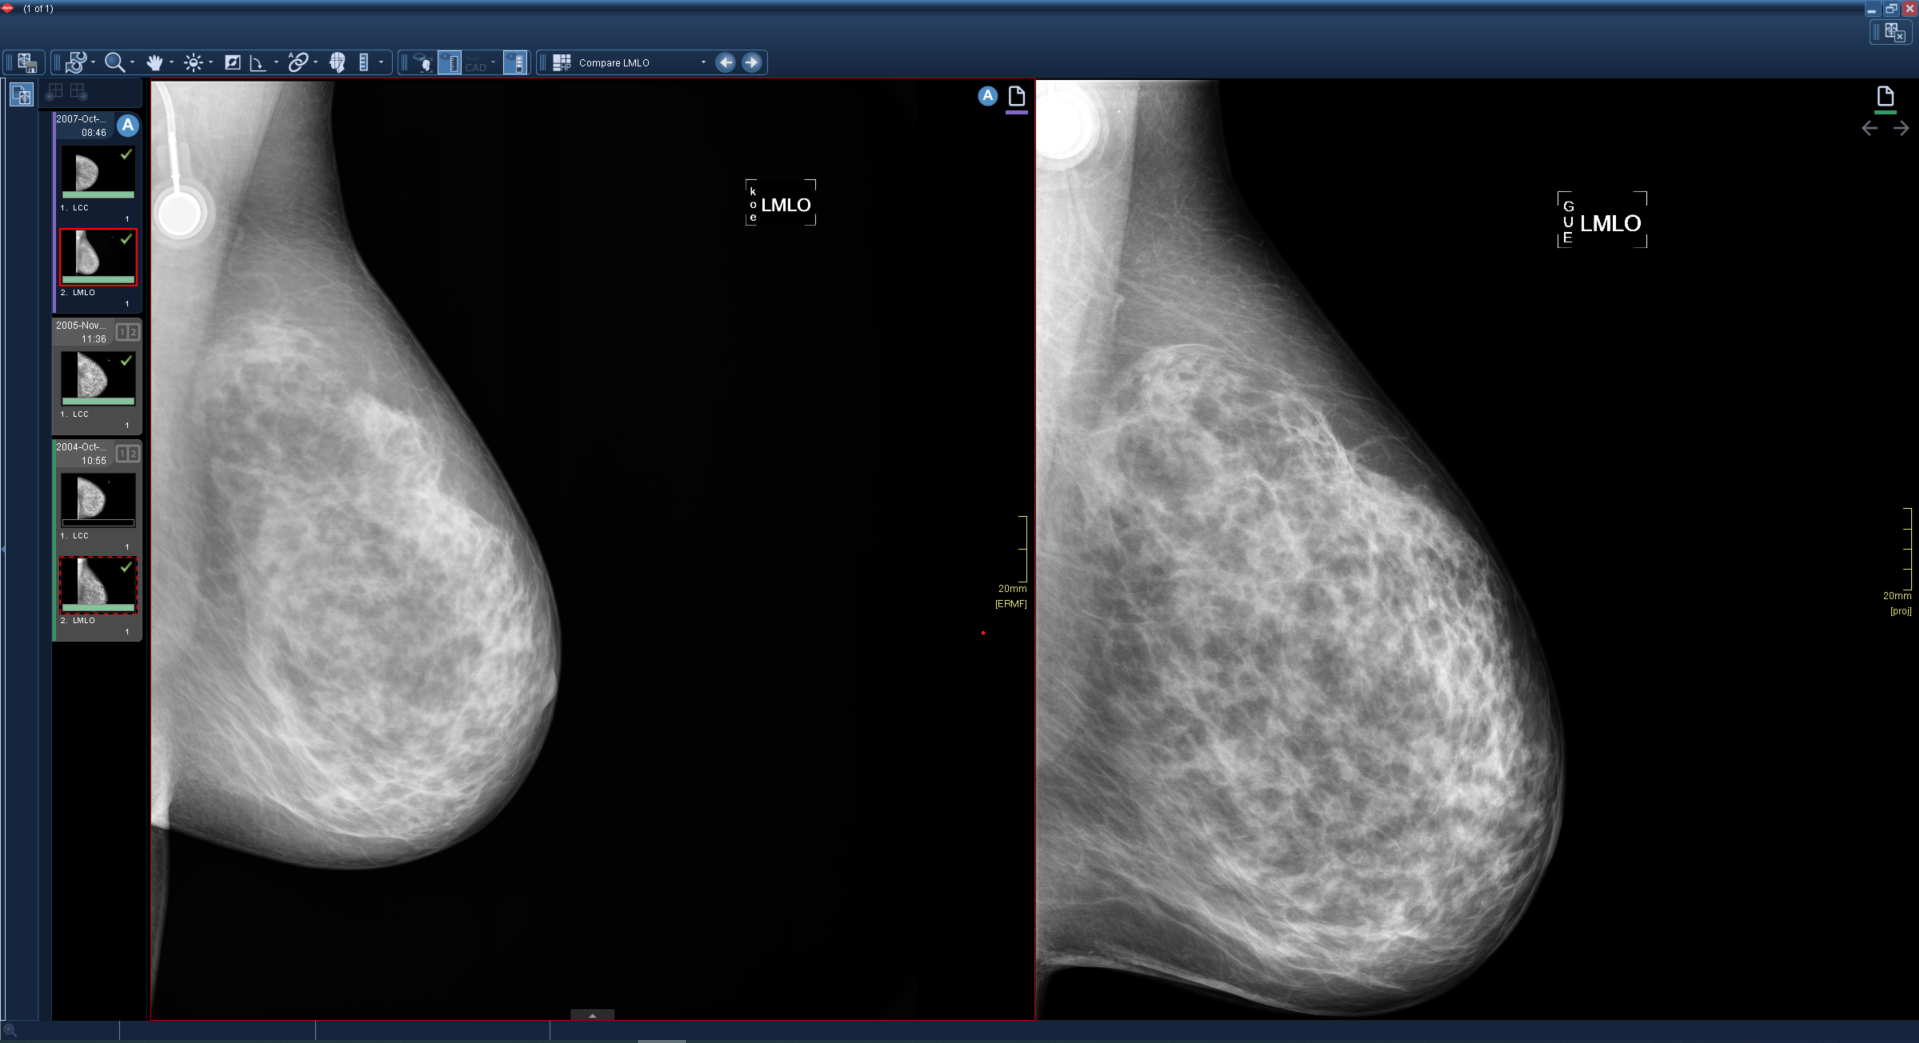

Όταν περνάτε με το ποντίκι πάνω από τα εικονίδια, αν υπάρχει διαθέσιμη συγκριτική εξέταση, το εικονίδιο επισημαίνεται και μπορεί να πατηθεί.

- Χρησιμοποιήστε τις συντομεύσεις πλοήγησης. Όλες οι συγκριτικές εξετάσεις σε προβολή εναλλάσσονται ανεξαρτήτως επιλεγμένου παραθύρου.

- Από προεπιλογή, με τον συνδυασμό πλήκτρων Alt + G όλες οι προγενέστερες εξετάσεις σε προβολή μετακινούνται στην προηγούμενη συγκριτική εξέταση. Αν η πιο πρόσφατη προγενέστερη εξέταση είναι ήδη σε προβολή, η συντόμευση προηγούμενης πλοήγησης δεν είναι διαθέσιμη.

- Από προεπιλογή, με τον συνδυασμό πλήκτρων Alt + H όλες οι προγενέστερες εξετάσεις σε προβολή μετακινούνται στην επόμενη συγκριτική εξέταση.

Οι συντομεύσεις πλοήγησης λειτουργούν μόνο σε εξετάσεις με την ίδια μονάδα με την ενεργή εξέταση. Αν έχετε πολλαπλές μονάδες, ενημερώνονται μόνο οι εικόνες εξέτασης της ενεργής μονάδας.